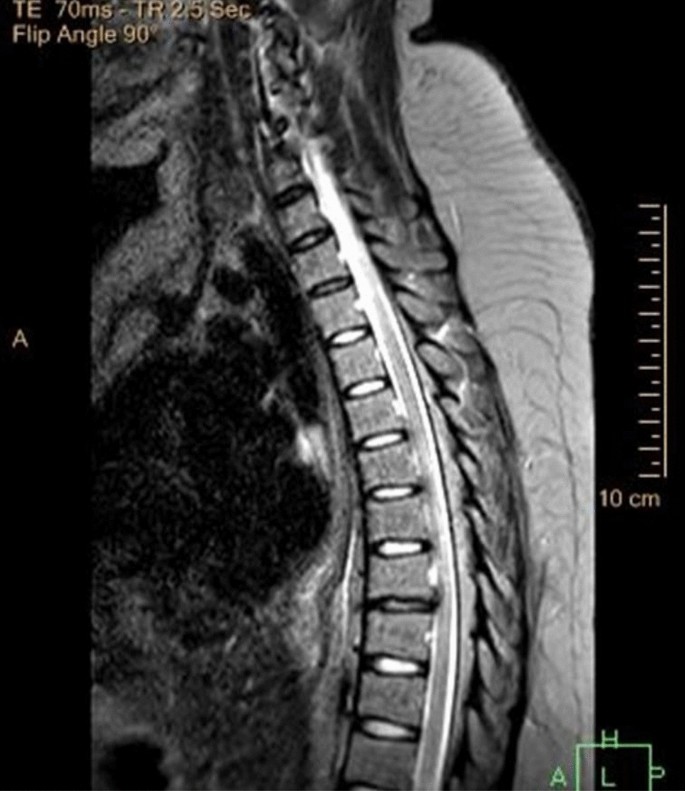

The MRI brain was completely normal. The MRI spine however showed diffuse cord atrophy with dorsal signal abnormality involving the lower cervical and thoracic spine, as shown in Figs. 1 and 2. These findings made us think of HIV-VM and subacute combined degeneration of the spinal cord.

Our patient presentation was atypical because she was virologically suppressed (VL < 20copies/ml), and her CD4 was 1051 cells/uL. It is important to remember that the CSF viral load measurement would have been essential to check for 'CSF viral escape'. We did not check for HIV-VL in the CSF looking for 'viral escape'. We did not have a large enough CSF sample to send for this test. Her confusion could have been due to HIV-NCD, but since she had nosocomial sepsis and hypokalaemia, it was not the only cause. Also, she had flaccid quadriplegia and absent global reflexes, which is not typical for HIV-VM. Blood showed hypokalaemia, which can explain an associated peripheral neuropathy worsened by HIV infection and subclinical hypothyroidism, but the weakness persisted despite the potassium correction. Vitamin B12 and folate levels were normal; this ruled out a subacute combined spinal cord degeneration. We did an extensive blood and CSF workup for other causes of weakness, which all came back negative. The spinal cord MRI supported the clinical suspicion and showed cord atrophy and T2-weighted hyperintensity of the cervicothoracic spine. We continued her cART and gave her a trial of IVIg, which did not improve the condition. In the ward, she developed nosocomial sepsis and died (Table 1).